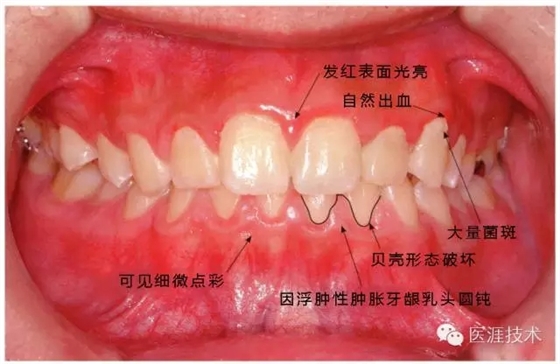

患牙齦炎的牙周組織的臨床圖像

640.webp (10).jpg

22歲男性牙齦炎的臨床圖像

640.webp (11).jpg

22歲男性,抽煙(1天約15根,煙齡5年)。刷牙狀態(tài)不佳。抽煙者特有的纖維性牙齦,未見發(fā)紅、腫脹。探針觸診,所有部位均出血。X線牙片未見骨吸收,診斷為牙齦炎。

14歲男性牙齦炎的臨床圖像

640.webp (12).jpg

14歲男性。刷牙狀態(tài)不佳。整顎浮腫性發(fā)紅、腫脹且刺激出血。牙頸部有早期齲(白斑)。

26歲男性牙齦炎的臨床圖像

640.webp (13).jpg

26歲男性。開口呼吸?;旌嫌醒例l發(fā)紅、腫脹與纖維性肥厚。菌斑干燥牢牢黏住,刷牙難以刷掉。